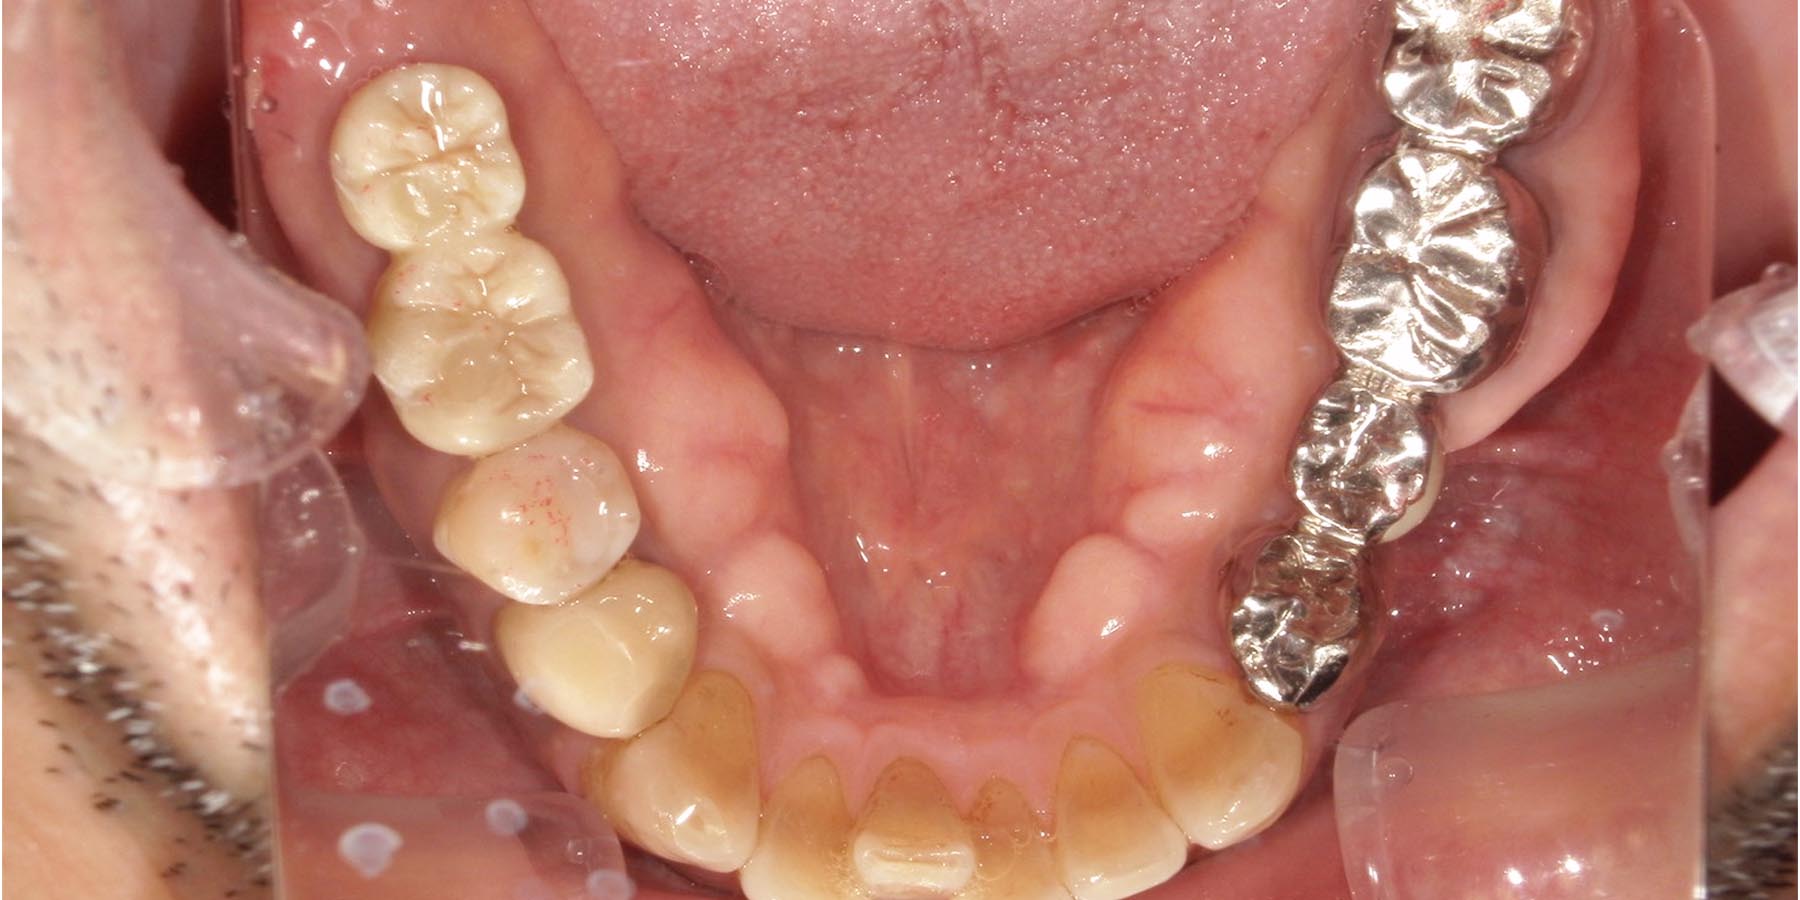

治療後

インプラント埋入後

被せ物セット完了